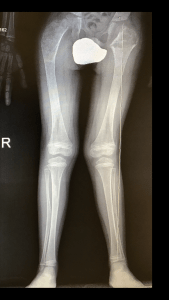

IMG_6182